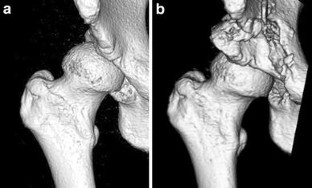

Fig. 2